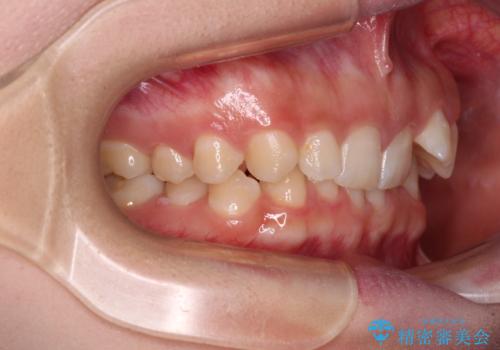

- 前歯のデコボコとディープバイトを気にして来院された患者様です。

左上前歯前方に飛び出しているため、歯列全体が前方に移動している状態でした。

左上の歯列は補助装置により速やかに移動し、1年程度で奥歯の咬み合わせが改善され、1年3ヶ月の短期間でしっかりと仕上げることができました。